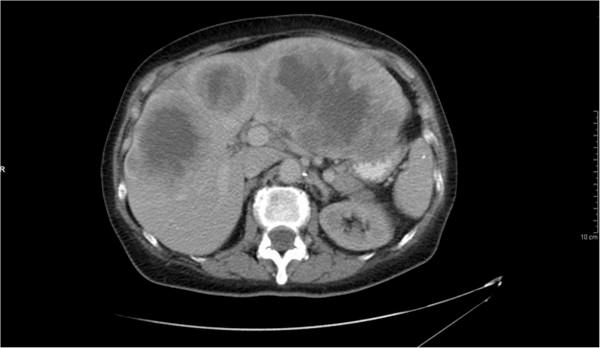

Our patient was a 64-year-old Caucasian woman who initially presented with urinary incontinence and was found to have a 14.5×9.0×9.0cm retroperitoneal solitary fibrous tumor compressing her bladder. Her tumor was surgically resected but recurred with multiple hepatic metastatic lesions. The hepatic metastases progressed despite systemic chemotherapy and treatment with doxorubicin transarterial chemoembolization. Her course was complicated by the development of recurrent fasting hypoglycemia, most likely secondary to Doege-Potter syndrome. Her hypoglycemia was managed with corticosteroid therapy and frequent scheduled nutrient intake overnight.

我们的患者是一名64岁的白种女性,最初表现为尿失禁,经检查发现有一个14.5×9.0×9.0厘米的腹膜后孤立性纤维瘤压迫她的膀胱。她的肿瘤接受了手术切除,但出现了多处肝转移灶复发。尽管进行了全身化疗和阿霉素经动脉化疗栓塞治疗,肝转移仍有进展。她的病程因反复出现空腹低血糖而变得复杂,最有可能继发于多伊格 - 波特综合征。她的低血糖通过皮质类固醇治疗和夜间频繁定时摄入营养物质进行管理。